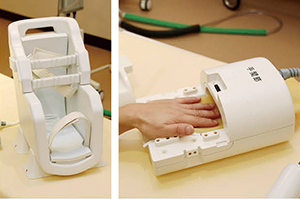

ワイドボアの広い検査空間や専用コイルの使い勝手を評価

WIT RF Coil Systemの足首用(左)と

手首用(右)のコイル

ECHELON OVALでは,“WIT RF Coil System”として,高感度受信とワークフローの短縮が可能なさまざまなコイルが利用できる。同院では,頭頸部用のNVコイル,足首や膝などの四肢関節撮像用のコイルを使用しているが,黒瀬TSは,「頭頸部用のNVコイルは,頭部と頸部を1回で撮像でき,広範囲の情報が必要な脳神経外科の術前検査などで連続撮像できるメリットは大きいです。コイル自体が軽く着脱も簡単で,撮像部位により近いセッティングができるので画質の向上も期待できます」と評価する。